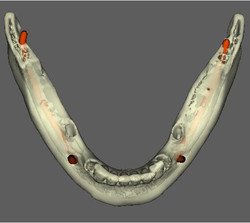

CIRURGIA GUIADA

REFORMATAÇÃO COM DENTALSLICE

Para trabalhar no DentalSlice basta solicitar na Clinica Serraro a tomografia computadorizada, onde as imagens DICOM (arquivos da tomografia) serão convertidas para o ambiente DentalSlice criando um arquivo que será enviado para o cirurgião dentista.

O Dental Slice é uma ferramenta de planejamento implantodôntico pré-operatório, desenhado para oferecer auxílio cirúrgico-protético com alto nível de precisão e aumentar a margem de segurança no tratamento.

O programa foi projetado para rodar em computadores pessoais e ambiente Windows.

O programa é acessível a qualquer cirurgião dentista e permite que o planejamento seja realizado pela própria equipe que vai realizar a cirurgia. As imagens também podem ser segmentadas, oferecendo melhor visualização de detalhes, como por exemplo do seio maxilar, canal da mandíbula ou de lesões.